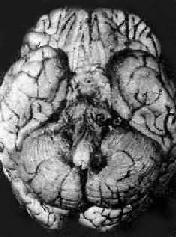

结核性脑膜炎

图18-14 结核性脑膜炎

脑基底部脑膜增厚,有散在的结核结节

病理变化以脑 底最明显。在脑桥脚间池视神经交叉大脑外侧裂等处之蛛网膜下腔内,有多量灰黄色混浊胶冻样渗出物积聚。偶见比粟粒还小的灰白色结核结节(图 18-14)。脑室脉络丛室管膜有时也可有结核结节形成。镜下,蛛网膜下腔内炎性渗出物主要由浆液、纤维素、巨噬细胞淋巴细胞组成,常有干酪样坏死, 偶见典型结核结节形成。病变严重者可累及脑皮质而引起脑膜脑炎。病程较长则可发生闭塞性血管内膜炎,从而可引起多发性脑软化。未经适当治疗致病程迁延的病 例,由于蛛网膜下腔渗出物的机化而发生蛛网膜粘连,可使第四脑室上中孔和外侧孔堵塞,引起脑积水